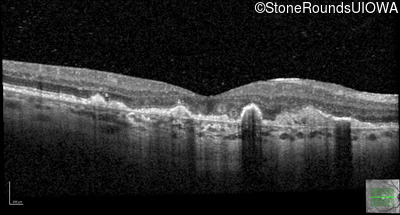

This 43 year old woman has experienced a gradual reduction in her central vision for the past 3 years.

| Malattia Leventinese | EFEMP1 | Arg345Trp CGG>TGG | AD |